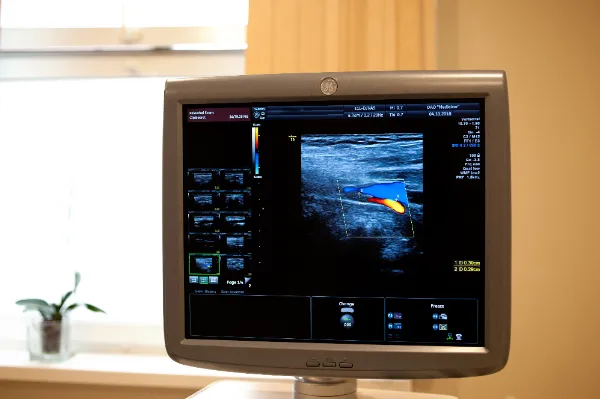

Проведение УЗИ пазух носа

Пациент ложится на кушетку, кожу над исследуемой зоной смазывают гелем. К местам локализации придаточных носовых пазух последовательно прикладывают датчик. На экране отображается состояние этих зон. Продолжительность обследования – до 10 минут.

Далеко не все диагностические центры выполняют данный тип УЗИ, ещё меньше сонологов, способных его осуществить. Наши врачи-диагносты в полной мере владеют техникой проведения такого исследования, а диагностическое отделение оборудовано новыми аппаратами от признанных мировых лидеров.